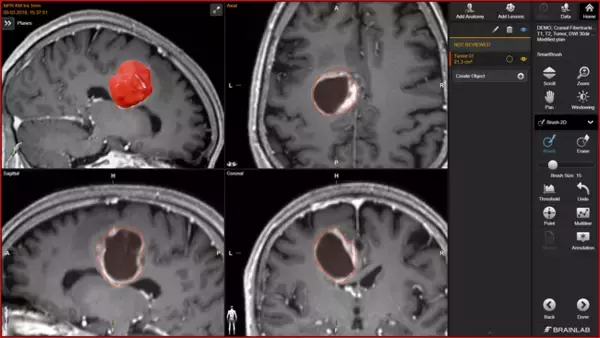

[画像2: https://prcdn.freetls.fastly.net/release_image/73157/15/73157-15-084b819f1dd9914d279562fa52e1f69d-3840x2160.jpg?width=536&quality=85%2C75&format=jpeg&auto=webp&fit=bounds&bg-color=fff ]

Brain Metastases イメージ図